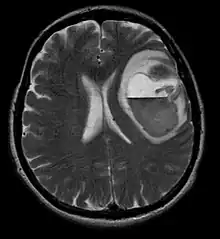

La tomodensitométrie (TDM) et L'imagerie par résonance magnétique (IRM) peuvent détecter efficacement une néoplasie dans le cerveau. L'IRM est plus sensible que la TDM pour identifier les lésions, mais présente des contre- indications pour les patients porteurs de stimulateurs cardiaques, de prothèses incompatibles, de clips métalliques et contre-indications. La TDM reste la méthode de choix pour détecter les calcifications au sein des lésions ou les érosions osseuses de la calotte ou de base du crâne. L'utilisation d' agents de contraste, iodés dans le cas du scanner et paramagnétiques (gadolinium) dans le cas de l'IRM, permet l'acquisition d'informations sur la vascularisation et l'intégrité de la barrière hémato-encéphalique, une meilleure définition de la tumeur tumorale par rapport à l' œdème environnant et à la génération d' hypothèses sur le degré de malignité. L'examen radiologique permet également d'évaluer les effets mécaniques et les modifications importantes des structures cérébrales résultant de la tumeur, telles que l' hydrocéphalie et les hernies, dont les effets peuvent être fatals. Enfin, en préparation à la chirurgie, ce diagnostic peut être utilisé pour déterminer la localisation de la lésion ou l'infiltration de la tumeur dans des zones vitales du cerveau. À cette fin, l'IRM est plus efficace que la tomodensitométrie car elle peut fournir des images en trois dimensions.

Les outils d'imagerie radiologique diagnostique mettent en évidence la modification du tissu néoplasique par rapport au parenchyme cérébral normal (par le biais de modifications de la densité tissulaire imagée électroniquement en TDM et de l'intensité du signal en IRM). Comme la plupart des tissus pathologiques, les tumeurs sont également reconnaissables par une accumulation accrue d'eau intracellulaire. Dans la tomodensitométrie, ils apparaissent hypodenses, c'est-à-dire de moindre densité que le parenchyme cérébral, dans la tomographie par résonance magnétique nucléaire avec relaxation spin-réseau hypointense et en relaxation spin-spin ainsi que l' hypersignal en pondération protonique (PD).

La zone saine du cerveau ne doit présenter aucune luminescence particulière sur une image radiologique. Par conséquent, il va sans dire que l'attention est portée sur des plages de signaux de contraste plus larges.

Dans le tissu tumoral, en général, la plus grande proportion d'amélioration du contraste est due à la barrière hémato-tumorale particulière qui permet le passage de l'iode (CT) et du gadolinium (IRM) dans l'espace interstitiel extravasculaire intratumoral. Cela augmente le signal (densité ou intensité) de la tumeur. Cependant, des précautions doivent être prises pour s'assurer que l'amélioration du contraste ne différencie pas définitivement la néoplasie de l'œdème péri-lésionnel. En fait, la découverte anatomo-pathologique dans le tissu tumoral infiltrant malin du gliome, comme dans le glioblastome et l'astrocytome anaplasique, montre également au-delà de l'œdème vasogénique causé par la destruction de la barrière hémato-encéphalique par la tumeur. Cette dernière condition clinique est difficilement détectable par imagerie diagnostique.

La tomodensitométrie du cerveau montre généralement une masse tissulaire qui peut être améliorée par l'un ou l'autre contraste. Au scanner, les gliomes de bas grade apparaissent généralement isodenses au parenchyme normal et peuvent donc ne pas présenter de rehaussement de contraste. De même, les lésions de la fosse crânienne postérieure sont difficiles à identifier au scanner. Par conséquent, les seuls résultats d'une telle tomographie ne sont pas toujours suffisants à des fins diagnostiques. Dans les cas douteux, l'utilisation de l'imagerie par résonance magnétique plus sensible est indispensable.

Sur-L'IRM montre une tumeur intracrânienne comme une lésion massive qui peut devenir plus luminescente après utilisation du produit de contraste. Cependant, il y a toujours une anomalie de signal dans -L'imagerie par résonance magnétique, qui indique la présence d'une néoplasie ou d'un œdème vasogénique. Habituellement, une luminescence accrue (amélioration du contraste) indique une tumeur d'un grade supérieur de malignité. Un anneau de contraste est caractéristique du glioblastome, avec la partie luminescente correspondant à la partie vitale de la tumeur maligne, et la plus foncée - zone hypointense correspondant à une nécrose tissulaire.